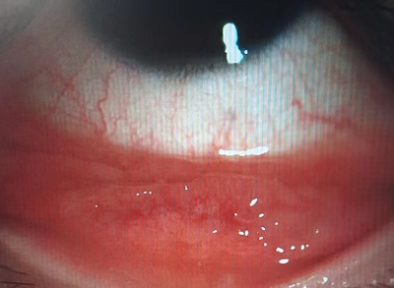

沙眼是一种常见的感染性眼病,是由微生物沙眼衣原体引起的一种慢性传染性结膜角膜炎,偶有急性发作。因其在睑结膜表面形成粗糙不平的外观,形似沙粒,故名沙眼。该病潜伏期5-14天,双眼患病,多发生于儿童或少年。感染沙眼可以延续数年以致数十年之久,其患病和病变的严重程度与环境卫生条件密切相关。

沙眼是由微生物沙眼衣原体感染所致的一种慢性传染性结膜角膜疾患,潜伏期约5~12日,双眼发病,儿童少年时期多发。因其在睑结膜表面形成粗糙不平的外观,形似沙砾,故名沙眼。对于出现沙眼早期症状的患者,需要及早就医控制病情,以防止进一步传播。